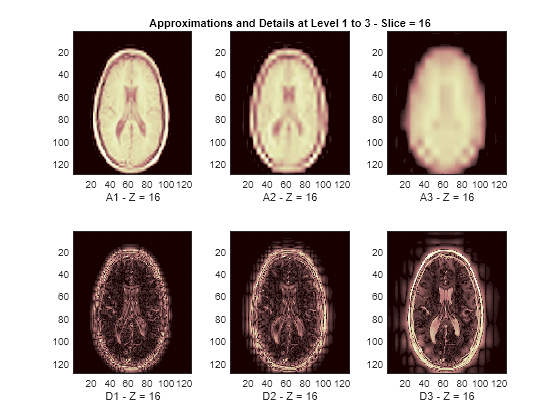

Display Lowpass and Highpass Components

The reconstructed approximations and details along the Z-orientation are displayed below.

nbIMG = 6; idxImages_New = [1 7 10 16 19 25]; for ik = 1:nbIMG j = idxImages_New(ik); figure('DefaultAxesXTick',[],'DefaultAxesYTick',[],... 'DefaultAxesFontSize',8,'Color','w') colormap(map) for k = 1:n labstr = [int2str(k) ' - Z = ' int2str(j)]; subplot(2,n,k) image(A{k}(:,:,j)) xlabel(['A' labstr]) if k==2 title(['Approximations and Details at Level 1 to 3 - Slice = ' num2str(j)]) end subplot(2,n,k+n) imagesc(abs(D{k}(:,:,j))) xlabel(['D' labstr]) end end